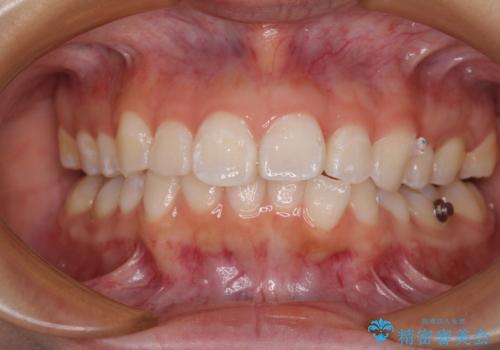

- 上下前歯の叢生を気にして来院された患者様です。

インビザラインでの治療を希望されていて、デコボコの程度が中等度であり、安価なパッケージにて対応可能と判断されたため、インビザライン・モデレートを用いて矯正治療を行うこととしました。